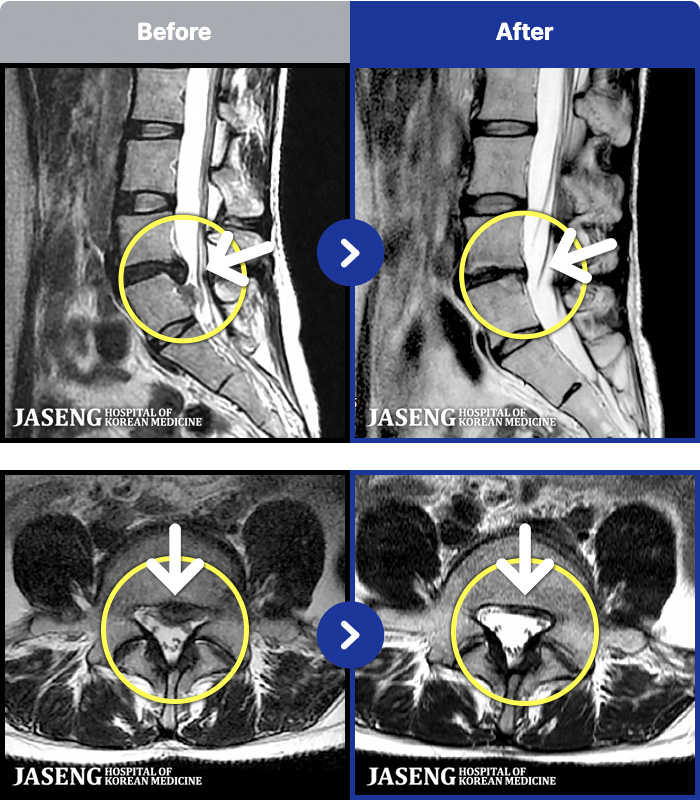

1,240 MRI ũ ʸ Ȯϼ.

MRI ġ

㸮 ϻ .